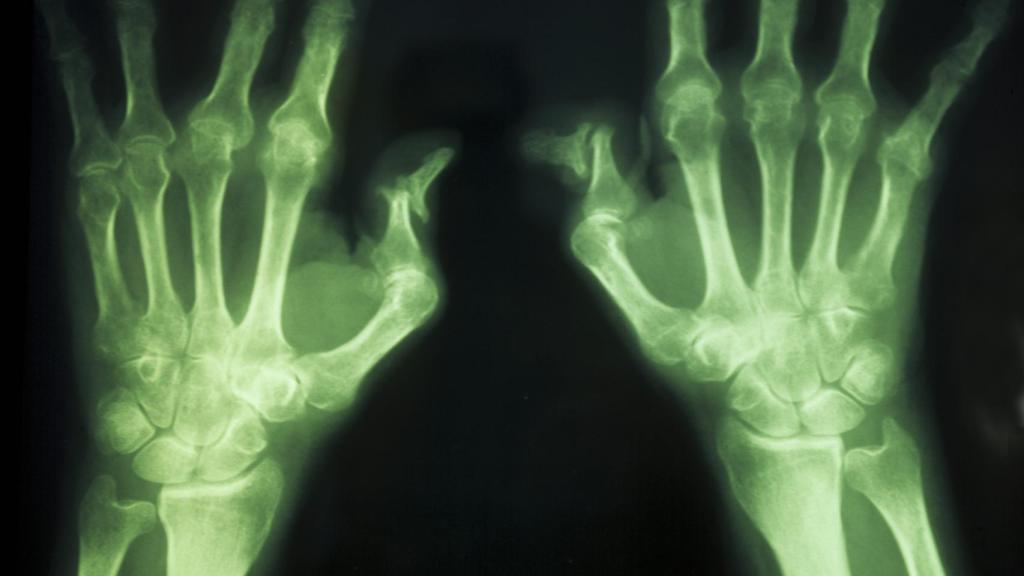

Las lesiones en las manos de una persona artrítica.

Las lesiones en las manos de una persona artrítica. Gtres